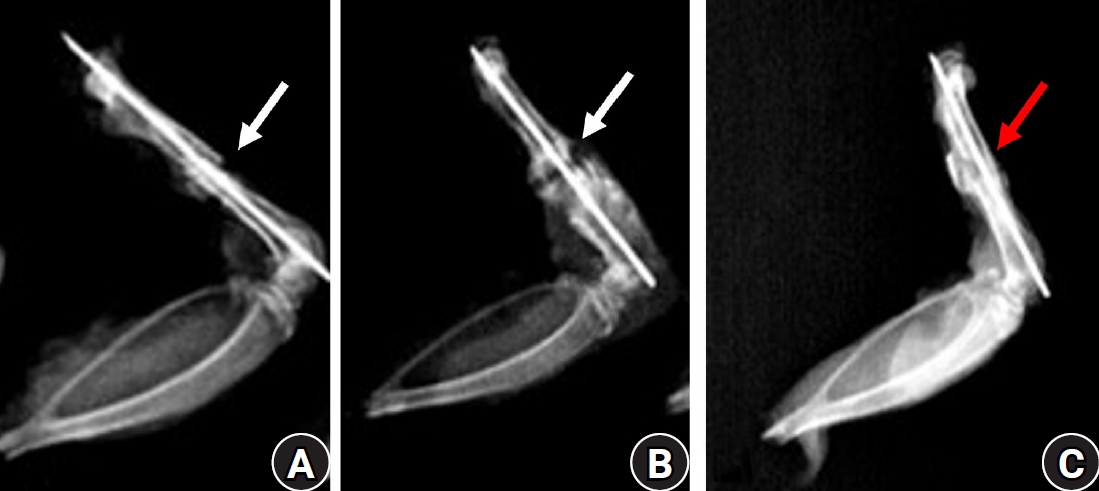

Thirty-six male Wistar (standard outbred) albino rats weighing 200–400 g underwent standardized mid-diaphyseal femoral fracture surgery. The animals were randomized into three groups (n=12 per group): group 1 received diclofenac sodium, group 2 received celecoxib, and group 3 served as the untreated control group received 1 mL distilled water orally once daily. Six rats from each group were euthanized at the end of the 2nd and 7th weeks after fracture for sample collection. Histological examination was complemented by immunohistochemical analysis, and the expression of type X collagen and vascular endothelial growth factor (VEGF) was assessed using the immunoreactive score (IRS) method.

Healing scores were significantly higher in the control group at both time points (2nd week, P=0.01; 7th week, P=0.03). At the 2nd week, rats treated with diclofenac sodium demonstrated significantly greater fibrosis (P=0.01), and by the 7th week, they exhibited impaired bone formation (P=0.003) along with increased bone defects (P=0.01). IRS values for type X collagen and VEGF were significantly higher in the control group than in both treatment groups during the 2nd week (P=0.01 and P=0.005, respectively).